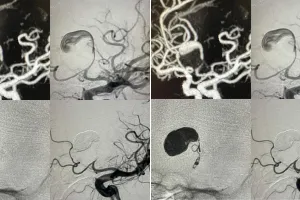

complex treatment done with endovascular simple coiling technique

शहर में आधुनिक न्यूरो-इंटरवेंशनल तकनीक की मदद से एक युवा मरीज के मस्तिष्क में पाए गए विशाल डिस्टल एंटीरियर सेरेब्रल आर्टरी एन्यूरिज्म का सफल उपचार किया गया। खास बात यह रही कि बिना ओपन ब्रेन सर्जरी के की गई इस जटिल प्रक्रिया के बाद मरीज को मात्र दूसरे दिन ही अस्पताल से छुट्टी दे दी।